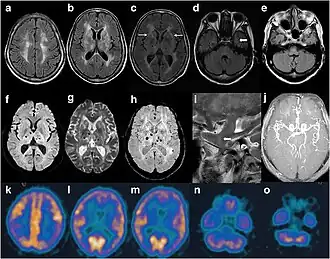

| Exame de imagem de paciente com IFF. Na ressonância magnética, vê-se sinais anormais na área área subcortical frontoparietal bilateral. Resultados de exame de ressonância magnética angiográfica exibiram separações distais de artérias cerebrais | |